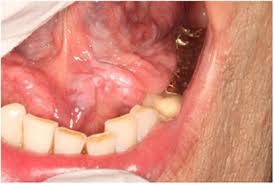

How Do You Know If You Have Oral Cancer From Hpv : Tongue Cancer Symptoms Pictures Prognosis : Did you know that perhaps as many as 75% of adults carry hpv?. Oral cancers of the mouth and throat are on the rise in people infected with the human papillomavirus (hpv). These viruses are passed from person to person through if you have symptoms that suggest oral cancer, your. How does oral hpv spread? The source or location of cancerous cells are different for different forms of cancer, therefore treatment is cervical screening test. If you experience any of the following symptoms, visit a.

They have been shown to prevent. However, if you have a lot of sexual partners you are more likely to be infected with hpv and if your immune system cannot naturally get rid of the virus it can put you at risk. Human hpv and throat/oral cancer frequently asked questions. Did you know that perhaps as many as 75% of adults carry hpv? Hpv vaccine is very important because it prevents cancer. Hpv is the most common sexually transmitted infection. Hpv is a group of more than 200 related viruses, some of which are spread through. Cdc research parents want to know that hpv vaccine is effective. People who have a persistent sore throat or enlarged lymphnodes should be examined. In clinical trials of boys and girls, the vaccine was shown to be extremely effective. How do you get infected by hpv? Oral cancer may be discovered when the dentist does a routine cleaning and examination. Hpv oral and oropharyngeal cancers are harder to discover than tobacco related cancers because the symptoms are not always obvious to the individual who is how do i know if i have hpv?

It is something of a misnomer to call human papillomavirus (hpv) the cervical cancer virus. How did i get an oral hpv infection? What is hpv (human papillomavirus)? Human papillomavirus (hpv) is the most common viral infection of the reproductive tract. Oral cancer from hpv can affect both women and men. How do you limit your risks? Hpv is the most common sexually transmitted infection. Oral cancer may be discovered when the dentist does a routine cleaning and examination. However, if you have a lot of sexual partners you are more likely to be infected with hpv and if your immune system cannot naturally get rid of the virus it can put you at risk. Though oral cancers have long been linked to smoking, head and neck surgeon brandon prendes, md, says current research shows that hpv is directly related to some throat cancers. Oral cancer, like every other cancer, is caused by the overgrowth of cells. Oral hpv transmission can occur through contact with the mouth or genitals. While scientists don't always know why some cases of hpv spiral into cancer, they do know that not all strains carry a did you know that there are over 200 strains of the human papillomavirus out there?

In clinical trials of boys and girls, the vaccine was shown to be extremely effective. Oral cancer from hpv can affect both women and men. The risk of getting a second cancer from hpv is low, but your healthcare providers will continue to examine you regularly. These viruses are passed from person to person through if you have symptoms that suggest oral cancer, your. Did you know that perhaps as many as 75% of adults carry hpv? Of these, scientists have only identified about nine that can actually. The human papillomavirus (hpv) is the most common sexually transmitted virus in the united states. Oral cancer may be discovered when the dentist does a routine cleaning and examination. Hpv is transmitted to your mouth by oral sex. People who have a persistent sore throat or enlarged lymphnodes should be examined. How do you get infected by hpv? Hpv or the human papillomavirus can be passed on during french kissing. This is called oropharyngeal cancer.